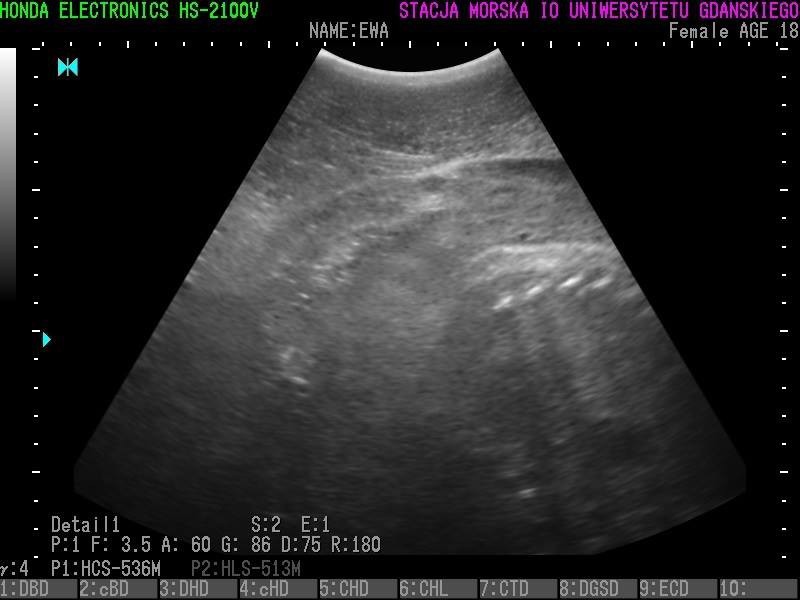

Wszystkie helskie foki - czyli Agata, Ewa, Unda Marina i Ania - są w ciąży. To wyniki badań ultrasonograficznych, które przeprowadzono w miniony piątek (23 grudnia).

• Z radością więc informujemy, że tego roku wszystkie nasze cztery samice spodziewają się potomstwa - czytamy na profilu Fokarium.